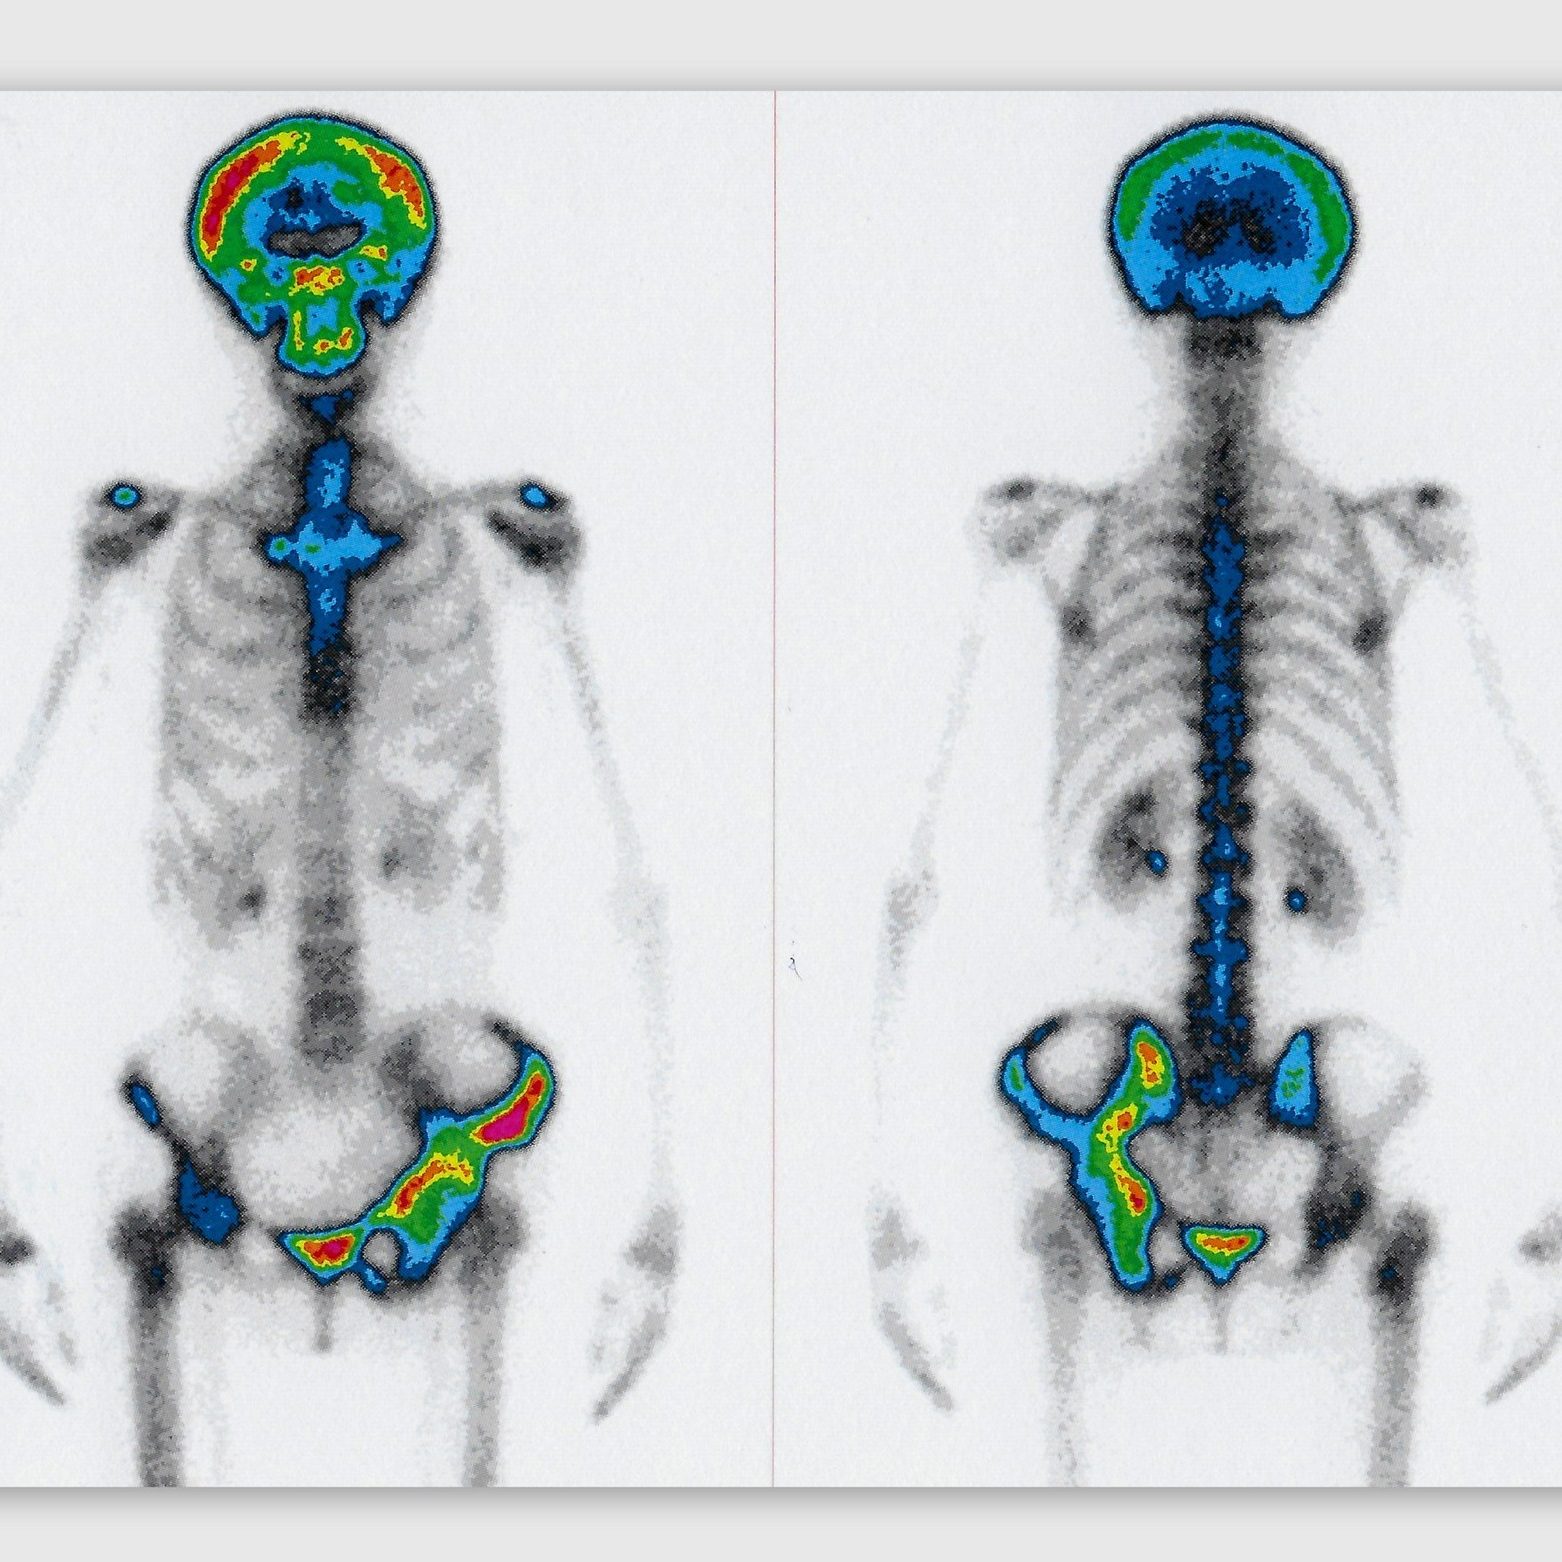

¿Cómo se realiza una gammagrafía ósea?

Una gammagrafía ósea implica inyectar una cantidad muy pequeña de material radiactivo (marcador) dentro de una vena. La sustancia viaja a través de la sangre hasta los huesos y órganos. A medida que esta va desapareciendo, emite un poco de radiación. Esta es detectada por una cámara que lentamente escanea el cuerpo.

Toma imágenes del marcador que hay en sus huesos. El técnico puede solicitarle que cambie de posición durante el procedimiento. Esto ayuda a obtener imágenes desde diferentes ángulos. Una gammagrafía ósea de todo el cuerpo tarda aproximadamente 1 hora en completarse.

¿Que detecta la cámara gamma?

La cámara gamma detecta las emisiones de energía de la radiosonda en su cuerpo y las convierte en una imágen. La cámara gamma de por sí no emite ninguna radiación. Tiene detectores de radiación denominados cabezas de cámara gamma.